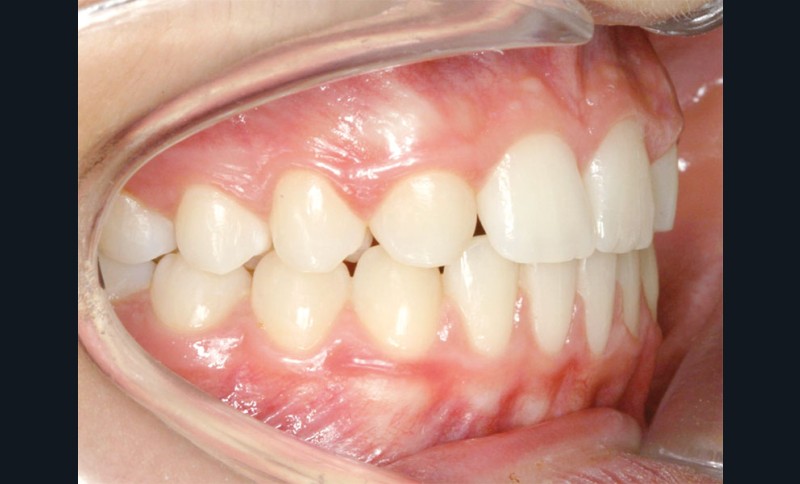

Les vues endo-buccales après extraction de 52 montrent des relations occlusales de classe II, un léger encombrement incisif mandibulaire et une tendance à la fermeture spontanée des espaces des incisives latérales confirmant le choix thérapeutique d’une fermeture d’espace (fig. 2).